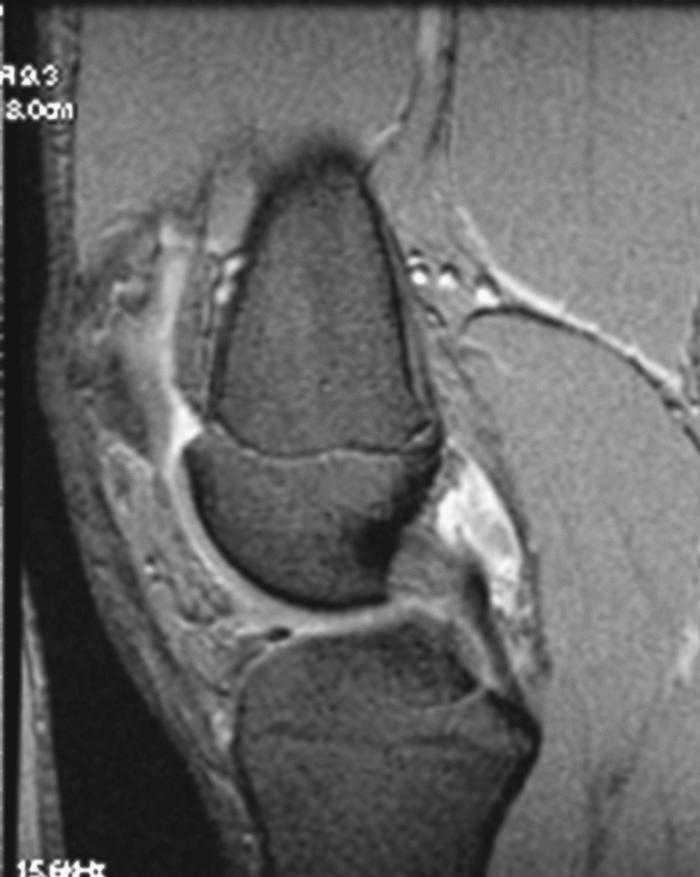

L'RM mostra (figs. 1, 3 i 5):

Figura 5 RM. Imatge potenciada en T1. Cossos lliures al voltant dels lligaments encreuats i en altres localitzacions intraarticulars.

• Múltiples cossos lliures intraarticulars.

• Lesió condral àmplia en faceta externa i cresta de ròtula, de gruix parcial.

• Vessament articular.

• Lligaments i meniscos i resta d'estructures íntegres.